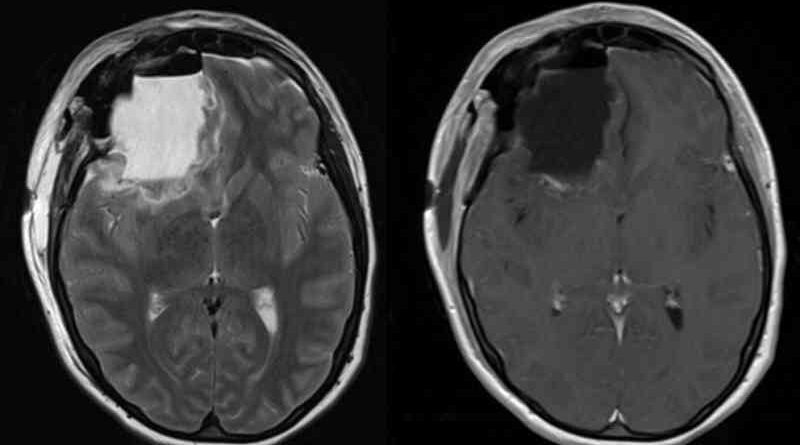

Mister medical: Peste 100 de absolvenți ai aceluiași liceu din New Jersey, SUA, au făcut o formă rară de cancer cerebral.

Peste 100 de persoane care au absolvit același liceu din New Jersey au fost diagnosticate cu forme rare de cancer